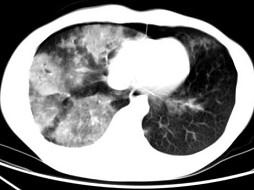

男,28岁,外伤后1小时行胸部CT如图,其最可能的诊断为 ( )A、肺癌B、双肺挫伤C、肺脓肿D、肺囊肿E、肺炎

问题 男,28岁,外伤后1小时行胸部CT如图,其最可能的诊断为 ( )

选项 A、肺癌 B、双肺挫伤 C、肺脓肿 D、肺囊肿 E、肺炎

答案 B